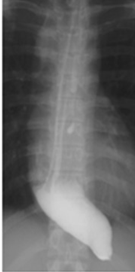

Gastrografin swallow - Esophagogastric anastomosis (stomach within the right hemithorax) (Courtesy Dr. V. Penopoulos)